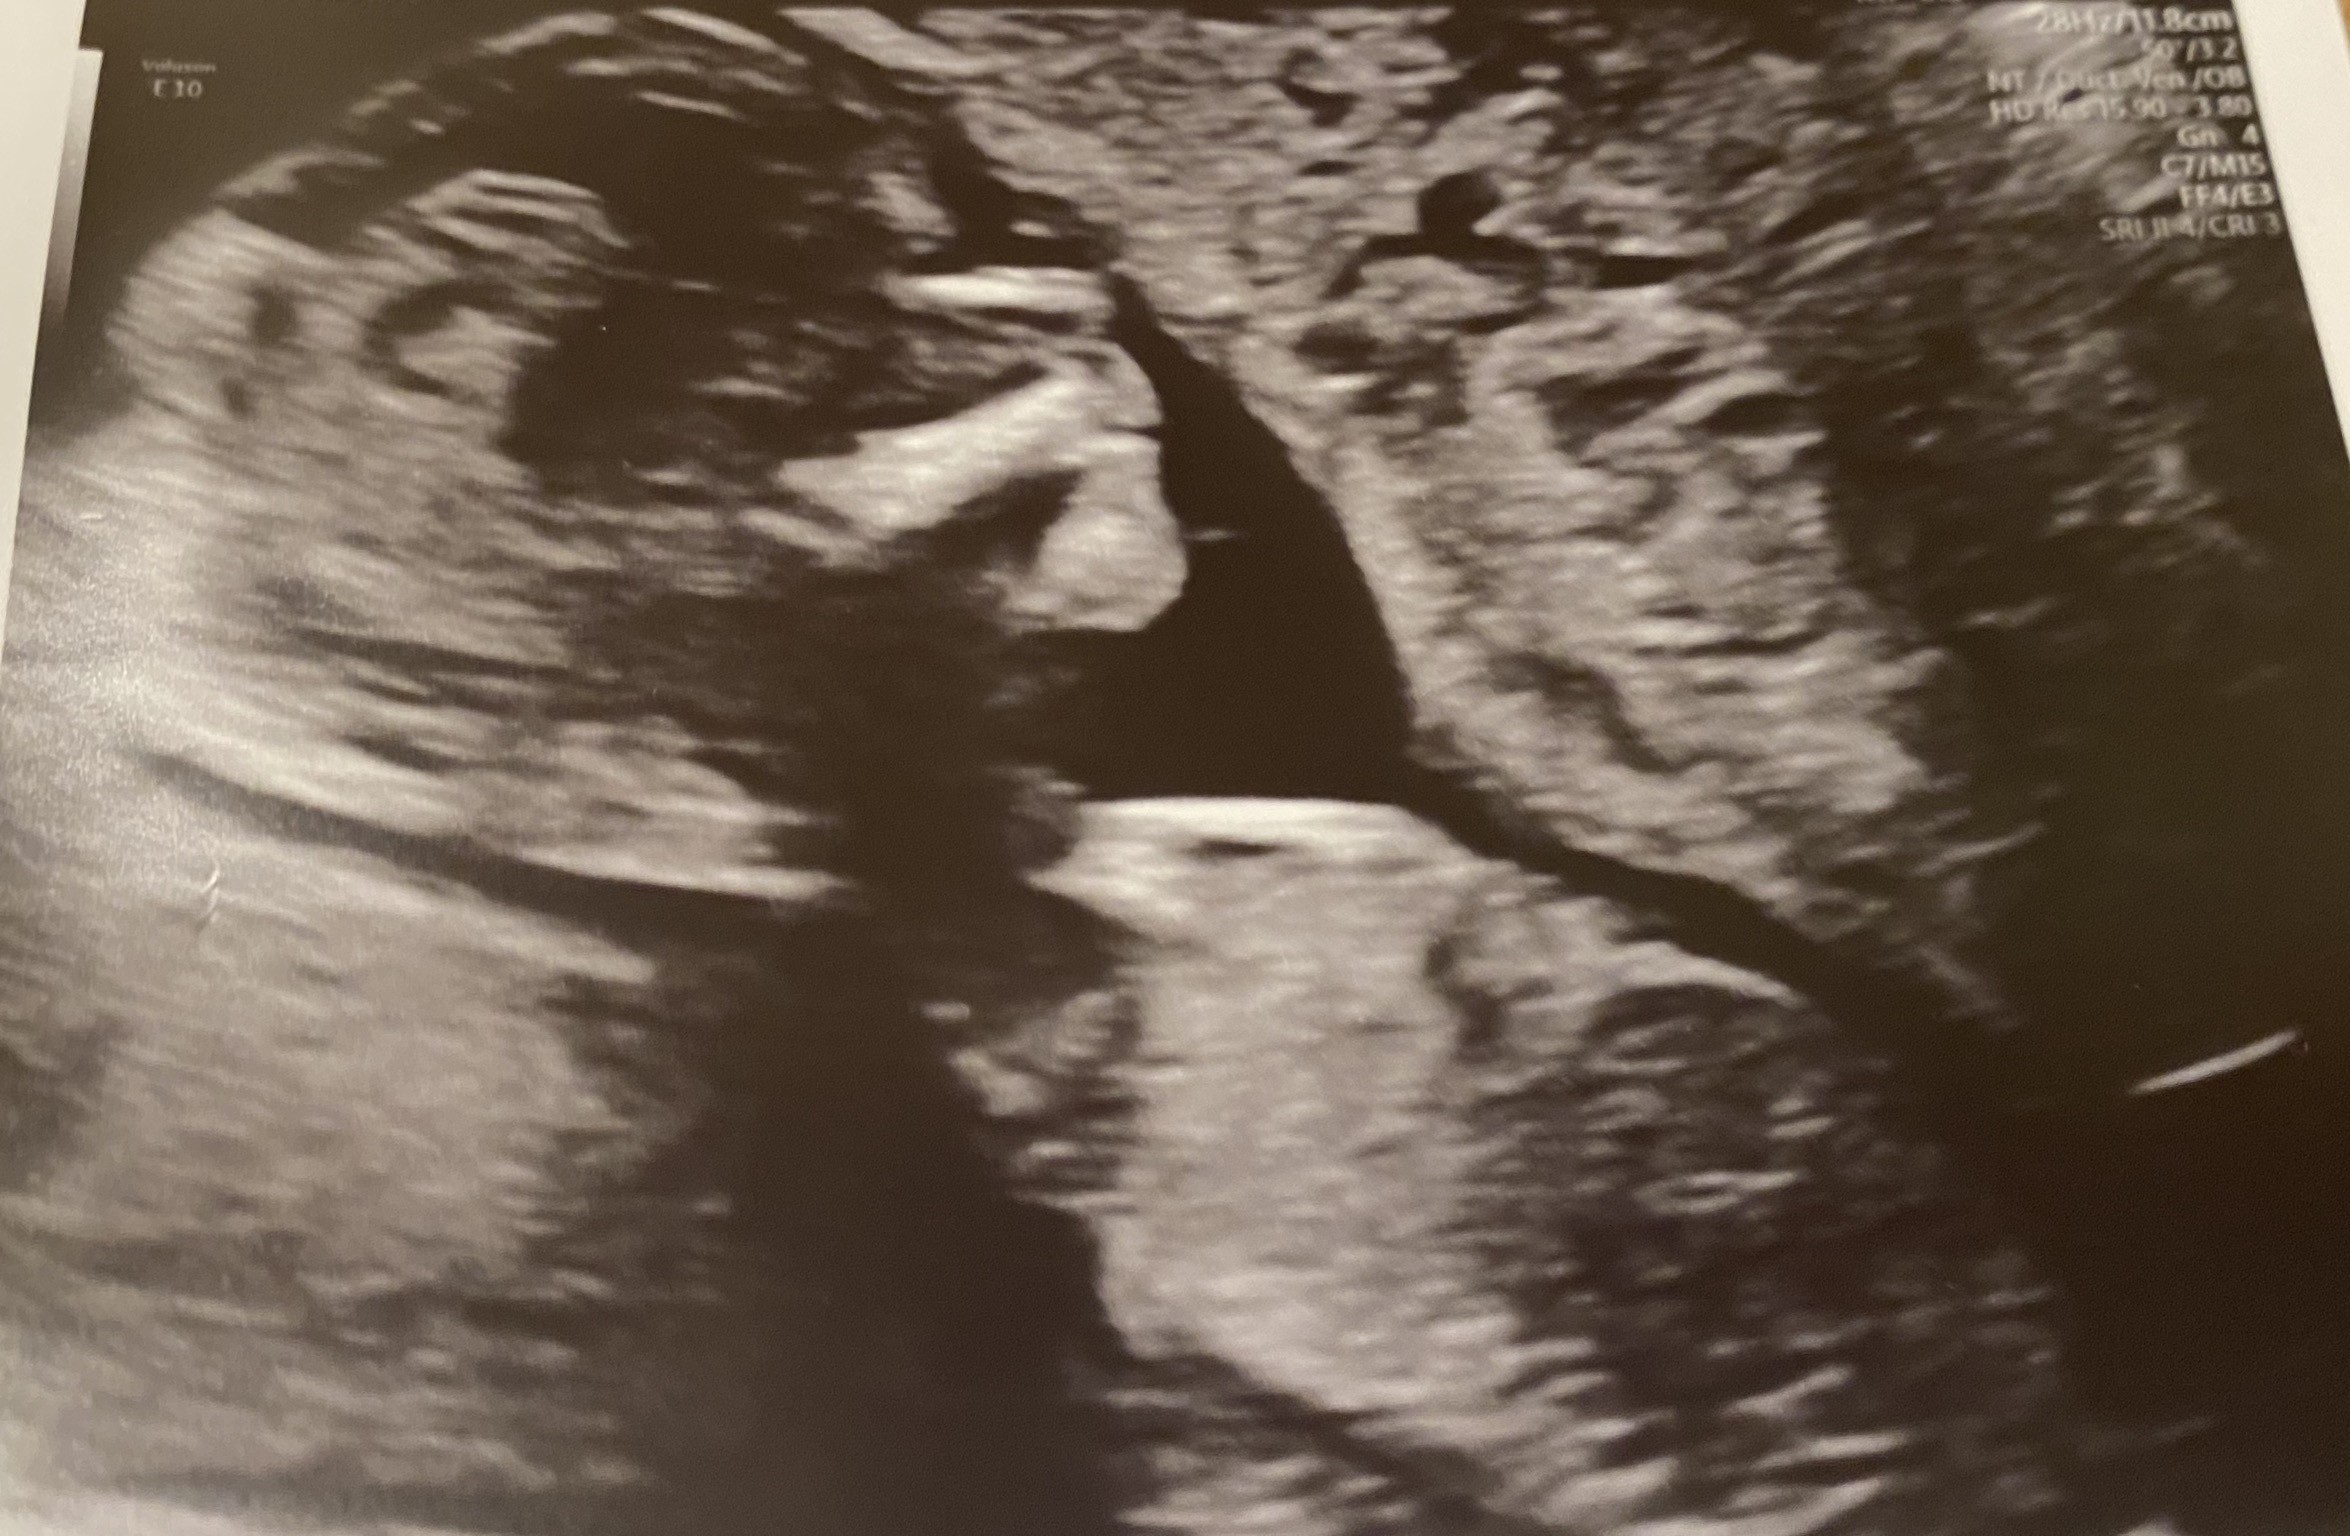

Dziękuje, wszystko w porządku 😊 jaka ulga. Krew pobrana teraz czekać na wyniki tylko ale jestem dobrej myśli. Skoro tyle przetrwało to te straty to był przypadek - tak sobie mówię. Mam dwoje zdrowych dzieci! Wiec to tez musi być!

Załączniki

• 8F3C78D8-6FF7-4DAA-82D3-B41154728411.jpeg

8F3C78D8-6FF7-4DAA-82D3-B41154728411.jpeg

611 KB · Wyświetleń: 89